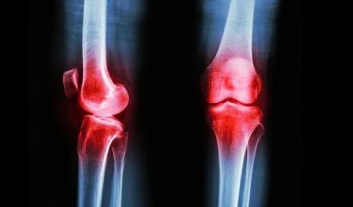

연골은 움직일 때 관절과뼈를 보호하는 쿠션입니다. 그러나 나이가 드신 분들이나 골관절염 환자의 경우에는 연골이 시간이 지남에 따라 마모되어 통증과 불편함을 유발할 수 있습니다.

골관절염은 노년기와 관련이 없는 경우가 많지만 연골은 모든 사람이 다양한 속도로 퇴화됩니다. 따라서 연령이나 상태에 관계없이 연골을 보호, 유지, 보충 및 복구할 수 있는 영양가 있는 음식을 섭취하는 것은 권장합니다.

연골 보호

골관절염은 전 세계 수백만 명의 사람들에게 영향을 미치는 질환입니다. 그러나 그것에 대한 보호하고 연골을 회복하는 방법과 음식이 있습니다.